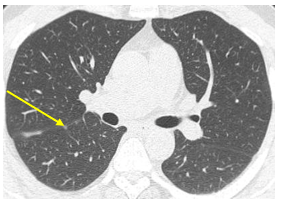

Chụp cắt lớp vi tính lồng ngực: Hình ảnh các nốt kính mờ rãnh liên thùy và màng phổi phải kích thước 2x3mm. Đám dải xẹp phổi thùy giữa phổi phải

Hình 6: Hình ảnh chụp cắt lớp vi tính lồng ngực: nốt tổn thương u phổi phải nhỏ hơn ban đầu sau 3 tháng điều trị (mũi tên vàng)

Chụp cắt lớp vi tính lồng ngực: Hình ảnh các nốt kính mờ rãnh liên thùy và màng phổi phải. Đám dải xẹp phổi thùy giữa phổi phải

Hình 7: Hình ảnh chụp cắt lớp vi tính lồng ngực sau điều trị, tổn thương u giảm kích thước sau 6 tháng điều trị (mũi tên vàng)